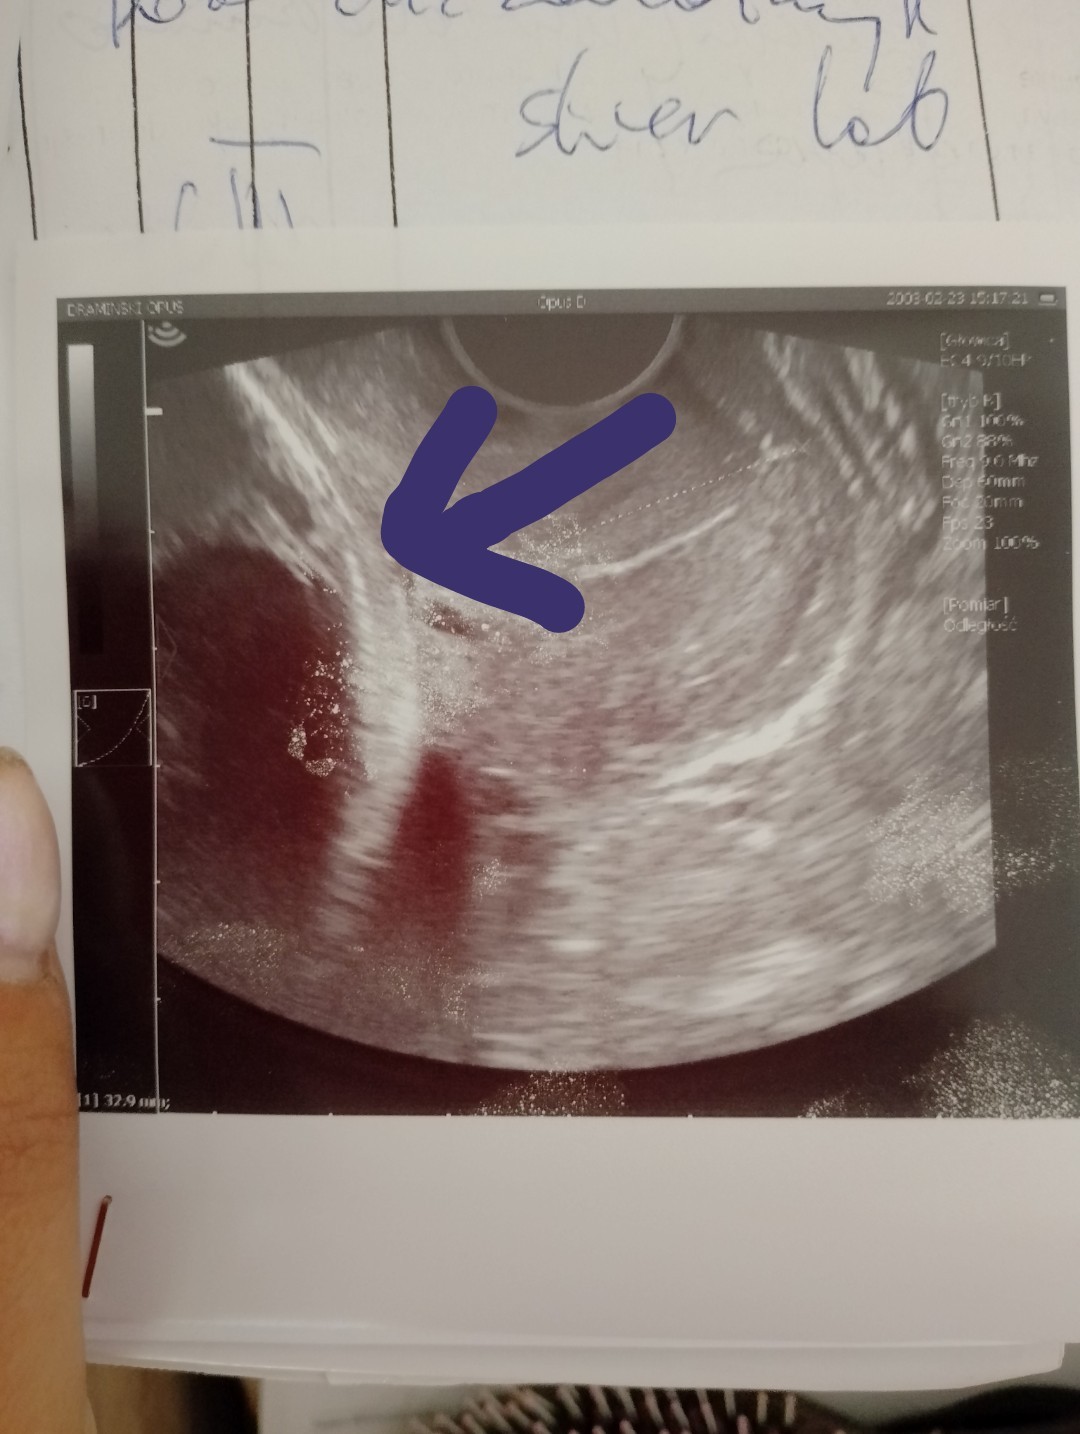

Ktoś mi może co to może być ? Czy to główka czy worek owodniowy? Lekarz mówił że wszystko w porządku ale zastanawia mnie co to jest

Załączniki

• IMG_20240706_094514_1.jpg

IMG_20240706_094514_1.jpg

201,4 KB · Wyświetleń: 124